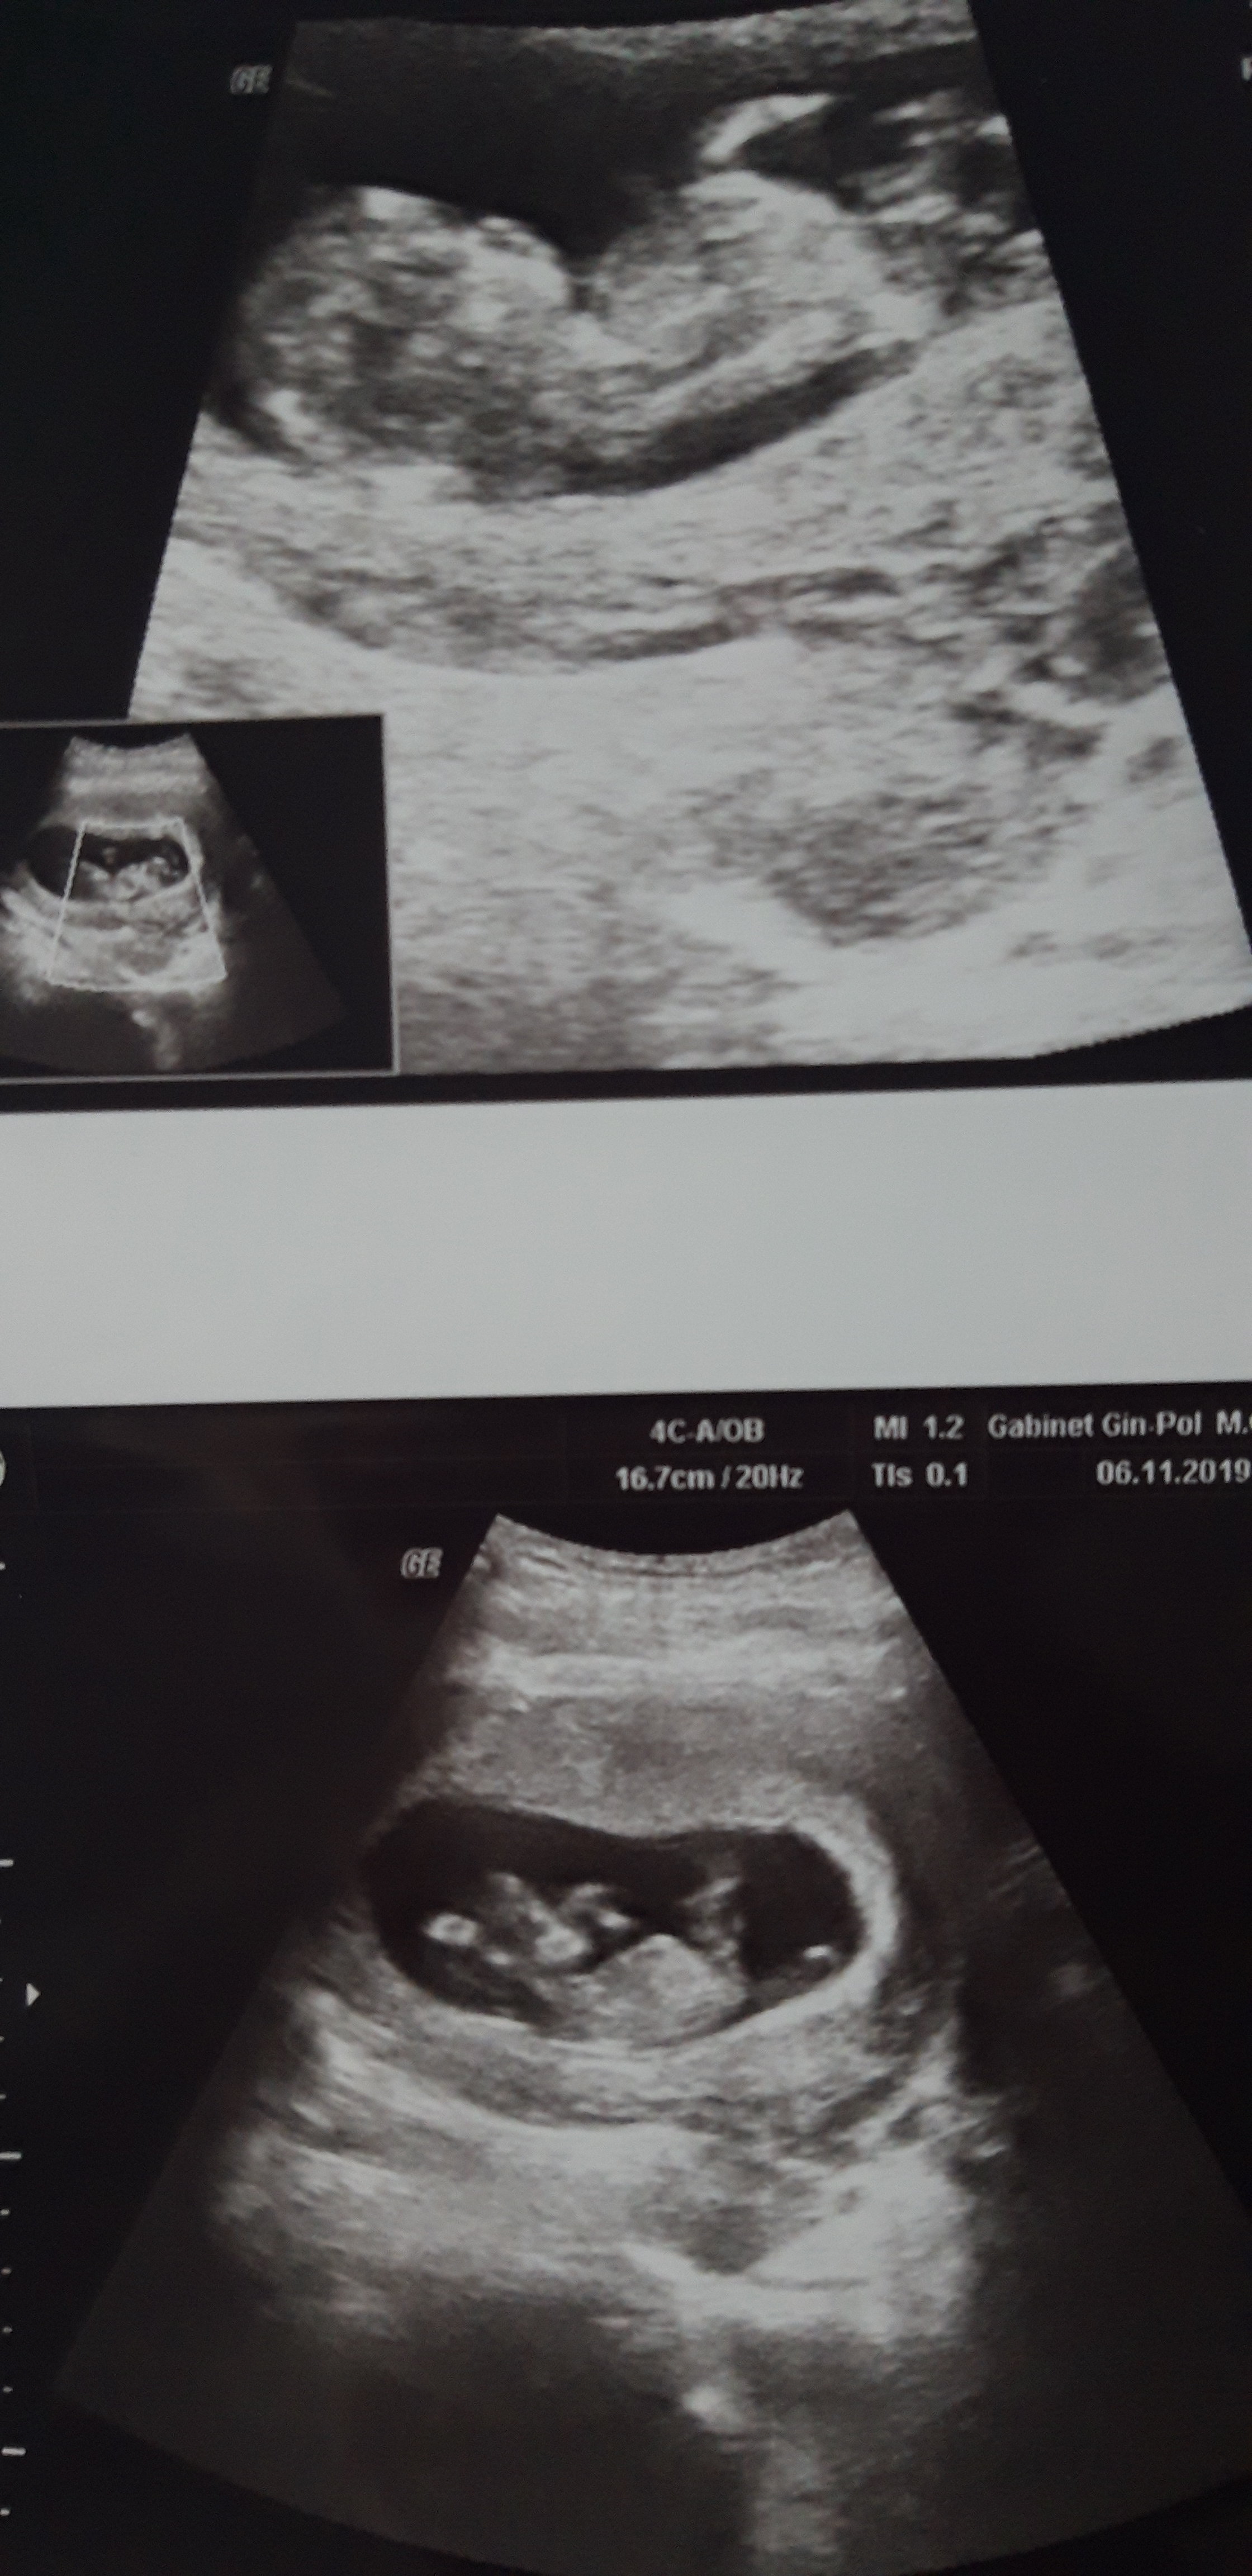

11+4

20191105_182001.jpeg

Na usg wiercił się niesamowicie, chyba zabiera mi całą energię bo ja chodzę półprzytomna ! No ale nie mam mu tego za złe ;) ;)